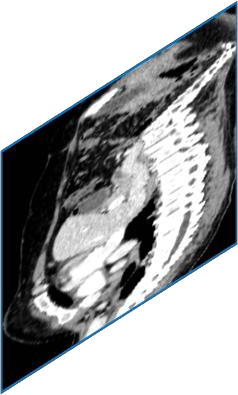

Due to the constraints of the imaging device and high cost in operation time, computer tomography (CT) scans are usually acquired with low intra-slice resolution. Improving the intra-slice resolution is beneficial to the disease diagnosis for both human experts and computer-aided systems. To this end, this paper builds a novel medical slice synthesis to increase the between-slice resolution. Considering that the ground-truth intermediate medical slices are always absent in clinical practice, we introduce the incremental cross-view mutual distillation strategy to accomplish this task in the self-supervised learning manner. Specifically, we model this problem from three different views: slice-wise interpolation from axial view and pixel-wise interpolation from coronal and sagittal views. Under this circumstance, the models learned from different views can distill valuable knowledge to guide the learning processes of each other. We can repeat this process to make the models synthesize intermediate slice data with increasing inter-slice resolution. To demonstrate the effectiveness of the proposed approach, we conduct comprehensive experiments on a large-scale CT dataset. Quantitative and qualitative comparison results show that our method outperforms state-of-the-art algorithms by clear margins.